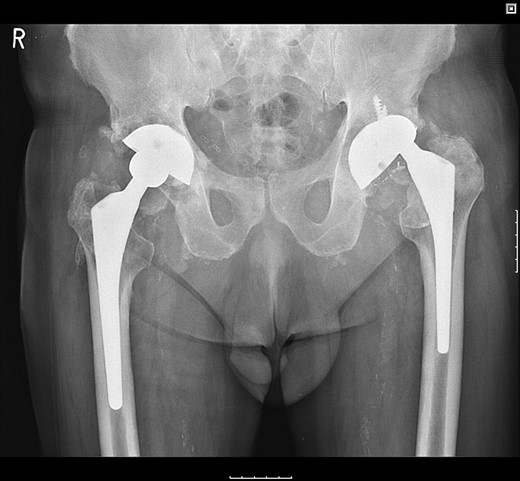

Pelvic radiographs demonstrated that the femoral head had migrated superolaterally through the polyethylene (PE) liner and the acetabular cup with metallic fragments inferior to this, and was articulating with the superior wall of the acetabulum causing bony destruction. There was no radiographic evidence of loosening to the stem (Fig. 1).

Pelvic radiograph demonstrating superolateral migration of the femoral head, metallic fragments around the neck and bony destruction of the acetabular wall.